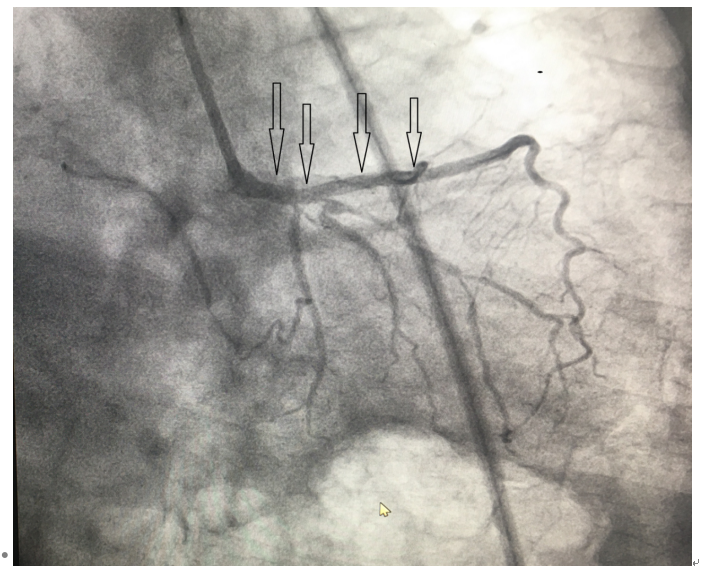

根据造影结果看,病变非常严重,介入处理累及左主干和前三叉的病变属于非常高危的操作,建议首选外科开胸处理。但胡大爷不想去外科搭桥,信任我们,愿意做冠脉介入治疗。郑全副主任医师、龙泉杉主治医师、梁婷主管护师,用三枚支架撑起了关键点,圆满完成手术。

(四)支架植入后效果